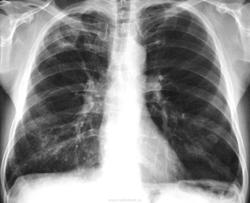

67 л. Вич-отрицательный. Пенсионер. Проведена проверочная флюорография перед операцией на коленном суставе. Флюорография в 2010 г. На контроль не вызывали. Архива нет. Кл. анализ крови - норма. Поликлиника намерена срочно направить в ПТД. Жду Ваших мнений коллеги. Nikolas.

Мое первое впечатление, что это периферический рак. После мнений врачей сайта такой уверенности не стало. Где-то прочитал, что при дифдиагностике круглых теней локализации процесса при не следует придавать слишком большое значение. Больной пока на стадии обследования. Я против непременной госпитализации в тубстационар из-за суперинфекции МБТ. В таких условиях и КУМ в содержимом бронхов могут найти. По мере поступления материалов обследования буду представлять на сайт. Тем не менее, обсуждение желательно продолжить. Развернутые мнения коллег о той или иной патологии было бы полезно для всех участников обсуждения. С уважением Nik.